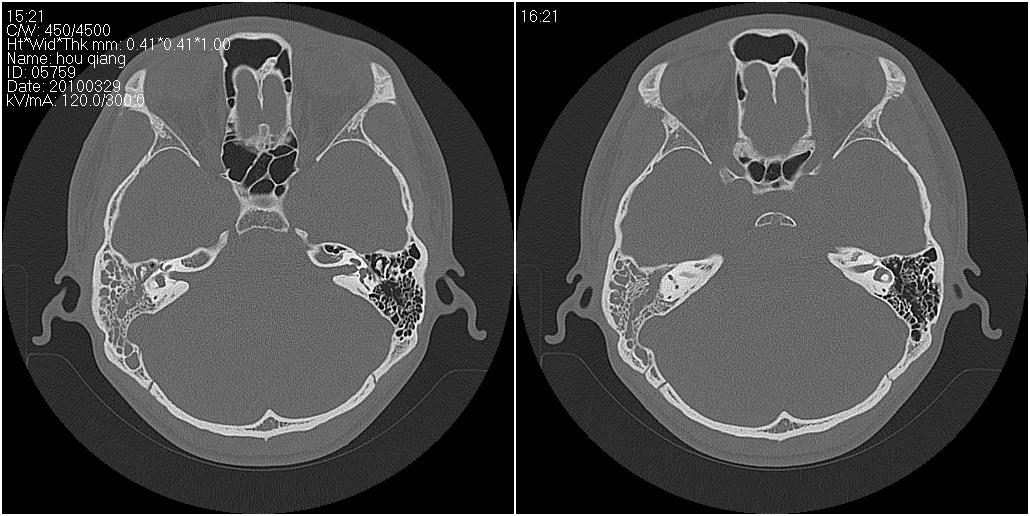

标题: CT25419:男性,18岁。右耳肿、痛5个多月。 [打印本页]

标题: CT25419:男性,18岁。右耳肿、痛5个多月。

右侧中耳乳突炎累及外耳道,鼻咽腺样体肥大。

1)右侧慢性中耳乳突炎并右侧中耳腔及外耳道肉芽肿或胆脂瘤形成。2)鼻咽腺样体肥大。